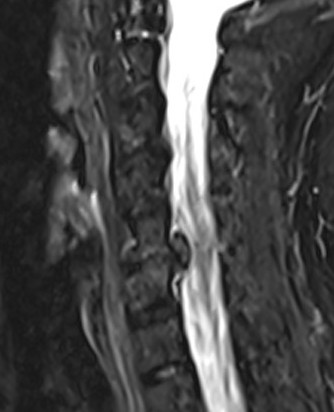

Paracentral disc

Foraminal disc